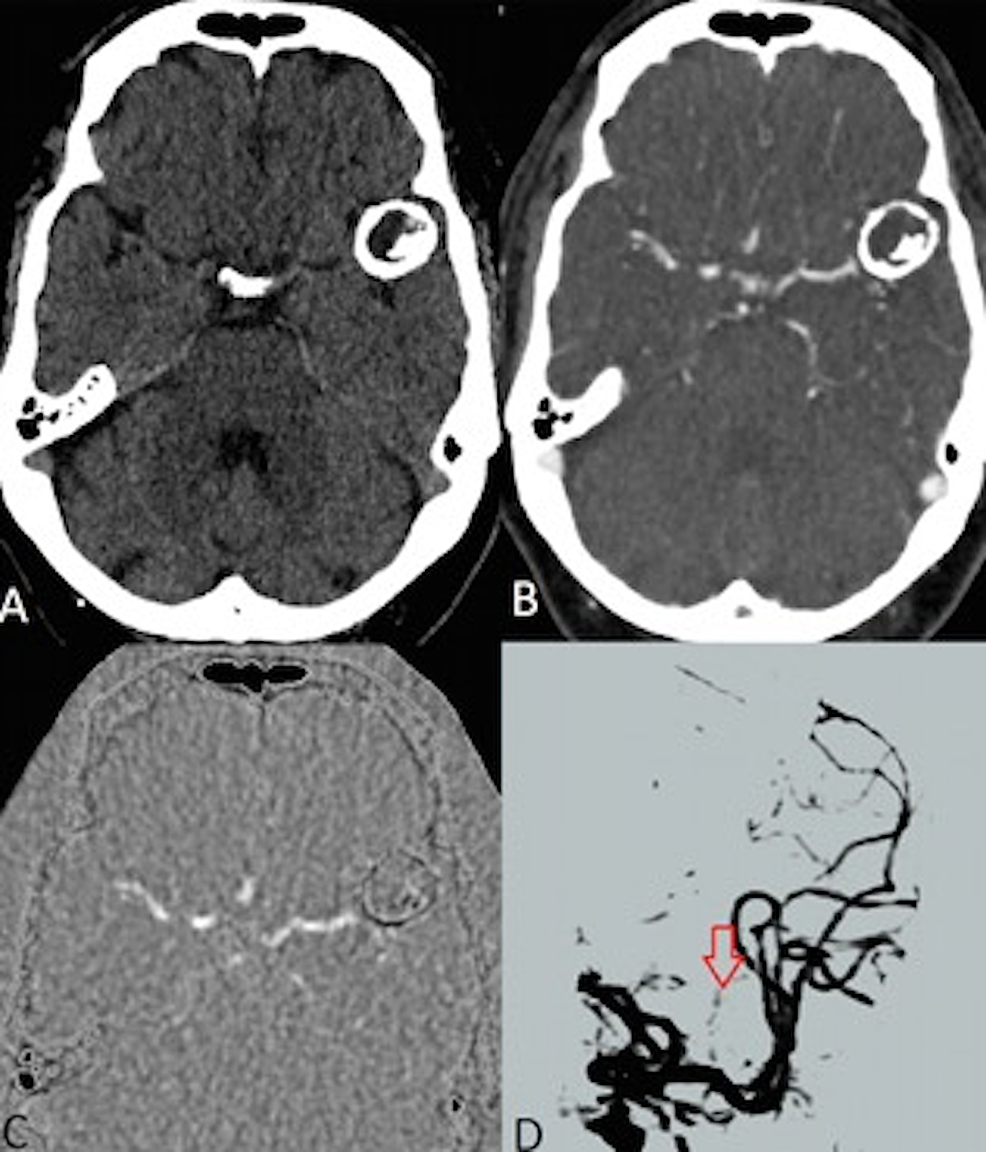

The patient was transferred to our hospital with a non-contrast head CT study done at the initial outside facility. The image showed a giant calcified left middle cerebral artery (MCA) mass upon admission to our academic medical center. A diagnostic cerebral angiogram and 4D-CTA study were ordered for further work-up and evaluation of aneurysmal blood flow. The angiogram showed no intracranial aneurysm opacification (Figure 1). Analysis of the 4D-CTA study showed a 2.7 x 2.4 x 3.0 cm left MCA calcified aneurysm with no internal enhancement on contrast images (Figure 2).

In this case, the diagnostic work-up of the patient allowed for comparing cerebral angiography and 4D-CTA imaging, techniques that have been widely used in the setting of diagnosing intracranial aneurysms. Both imaging modalities were used to assess rupture risk, and it was reassuring to discover that both yielded similar findings and ultimately showed no aneurysmal blood flow likely due to a completely thrombosed lumen. The angiogram showed no contrast filling of the calcified aneurysm, while the 4D-CTA showed no contrast opacification within the non-calcified component of the aneurysm.